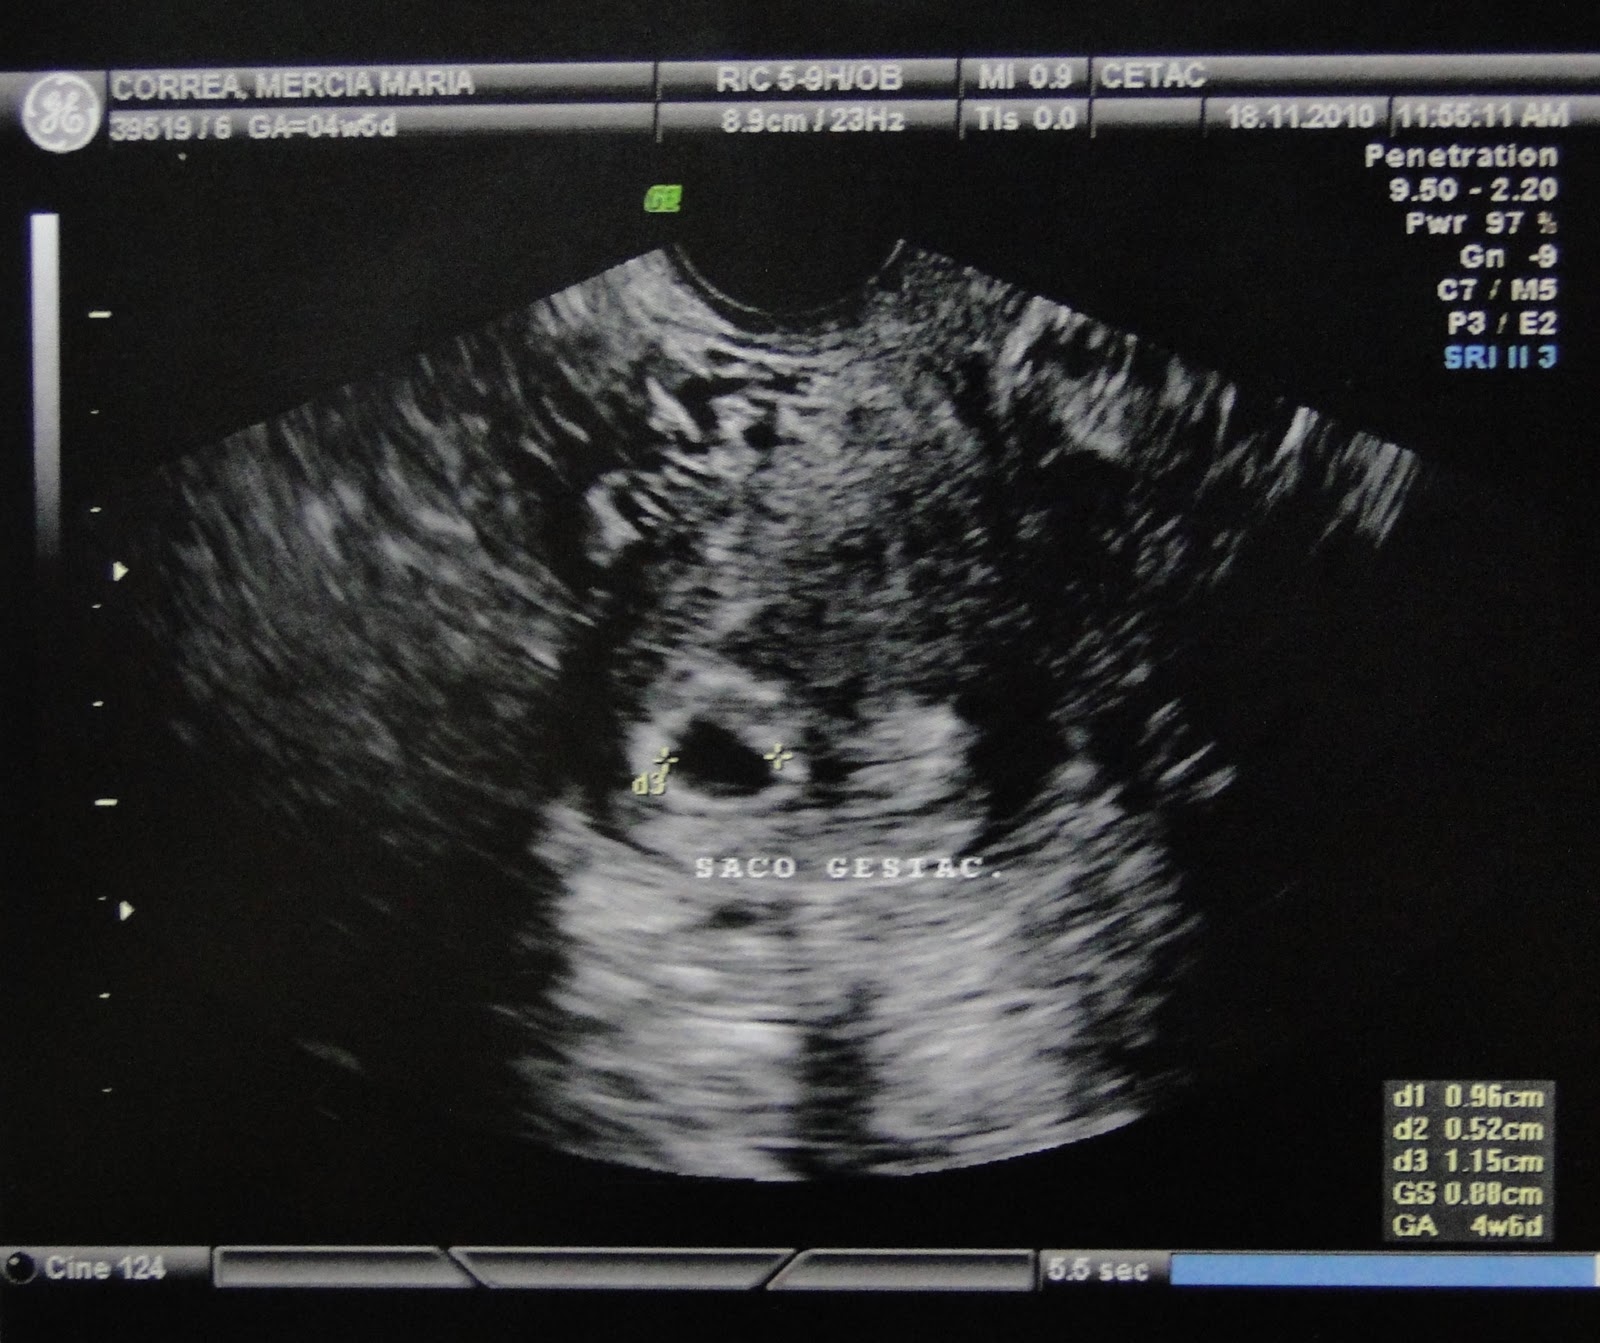

Ontem fizemos a primeira ultra do nosso bebezinho, foi pela manhã!

Só pudemos ver o saquinho gestacional, que possui 8,8mm e o corpo lúteo, que está bem vascularizado!

Ela explicou que o saquinho está bem implantado, bem no fundo do útero, e que está tudo ótimo, em níveis normais!

Confirmamos pelo exame que estou com 4 semanas e 6 dias.

Olhem aí!

O médico me pediu para repetir a ultra em uma semana e ver como está a evolução, talvez consigamos ver o embrião na próxima vez!! E na segunda-feira vou ao obstetra para levar a ultra e começar o pré-natal oficialmente!! Já estou ansiosa, vou perguntar um monte de coisas!!